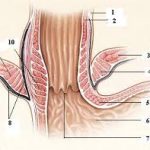

1. Östaki Borusu (Tuba Auditiva) Fonksiyonu ve Anatomisi

Östaki borusu, burun ve orta kulak arasında yer alan bir kanaldır ve orta kulağın havalanmasını, basınç dengelenmesini ve salgıların drenajını sağlar.

Çocuklarda Östaki borusu daha kısa, daha yatay ve daha dar olduğundan, tıkanmaya daha eğilimlidir.

Adenoid dokusu nasofarenkste, Östaki borusunun açıldığı bölgeye yakın bulunur.